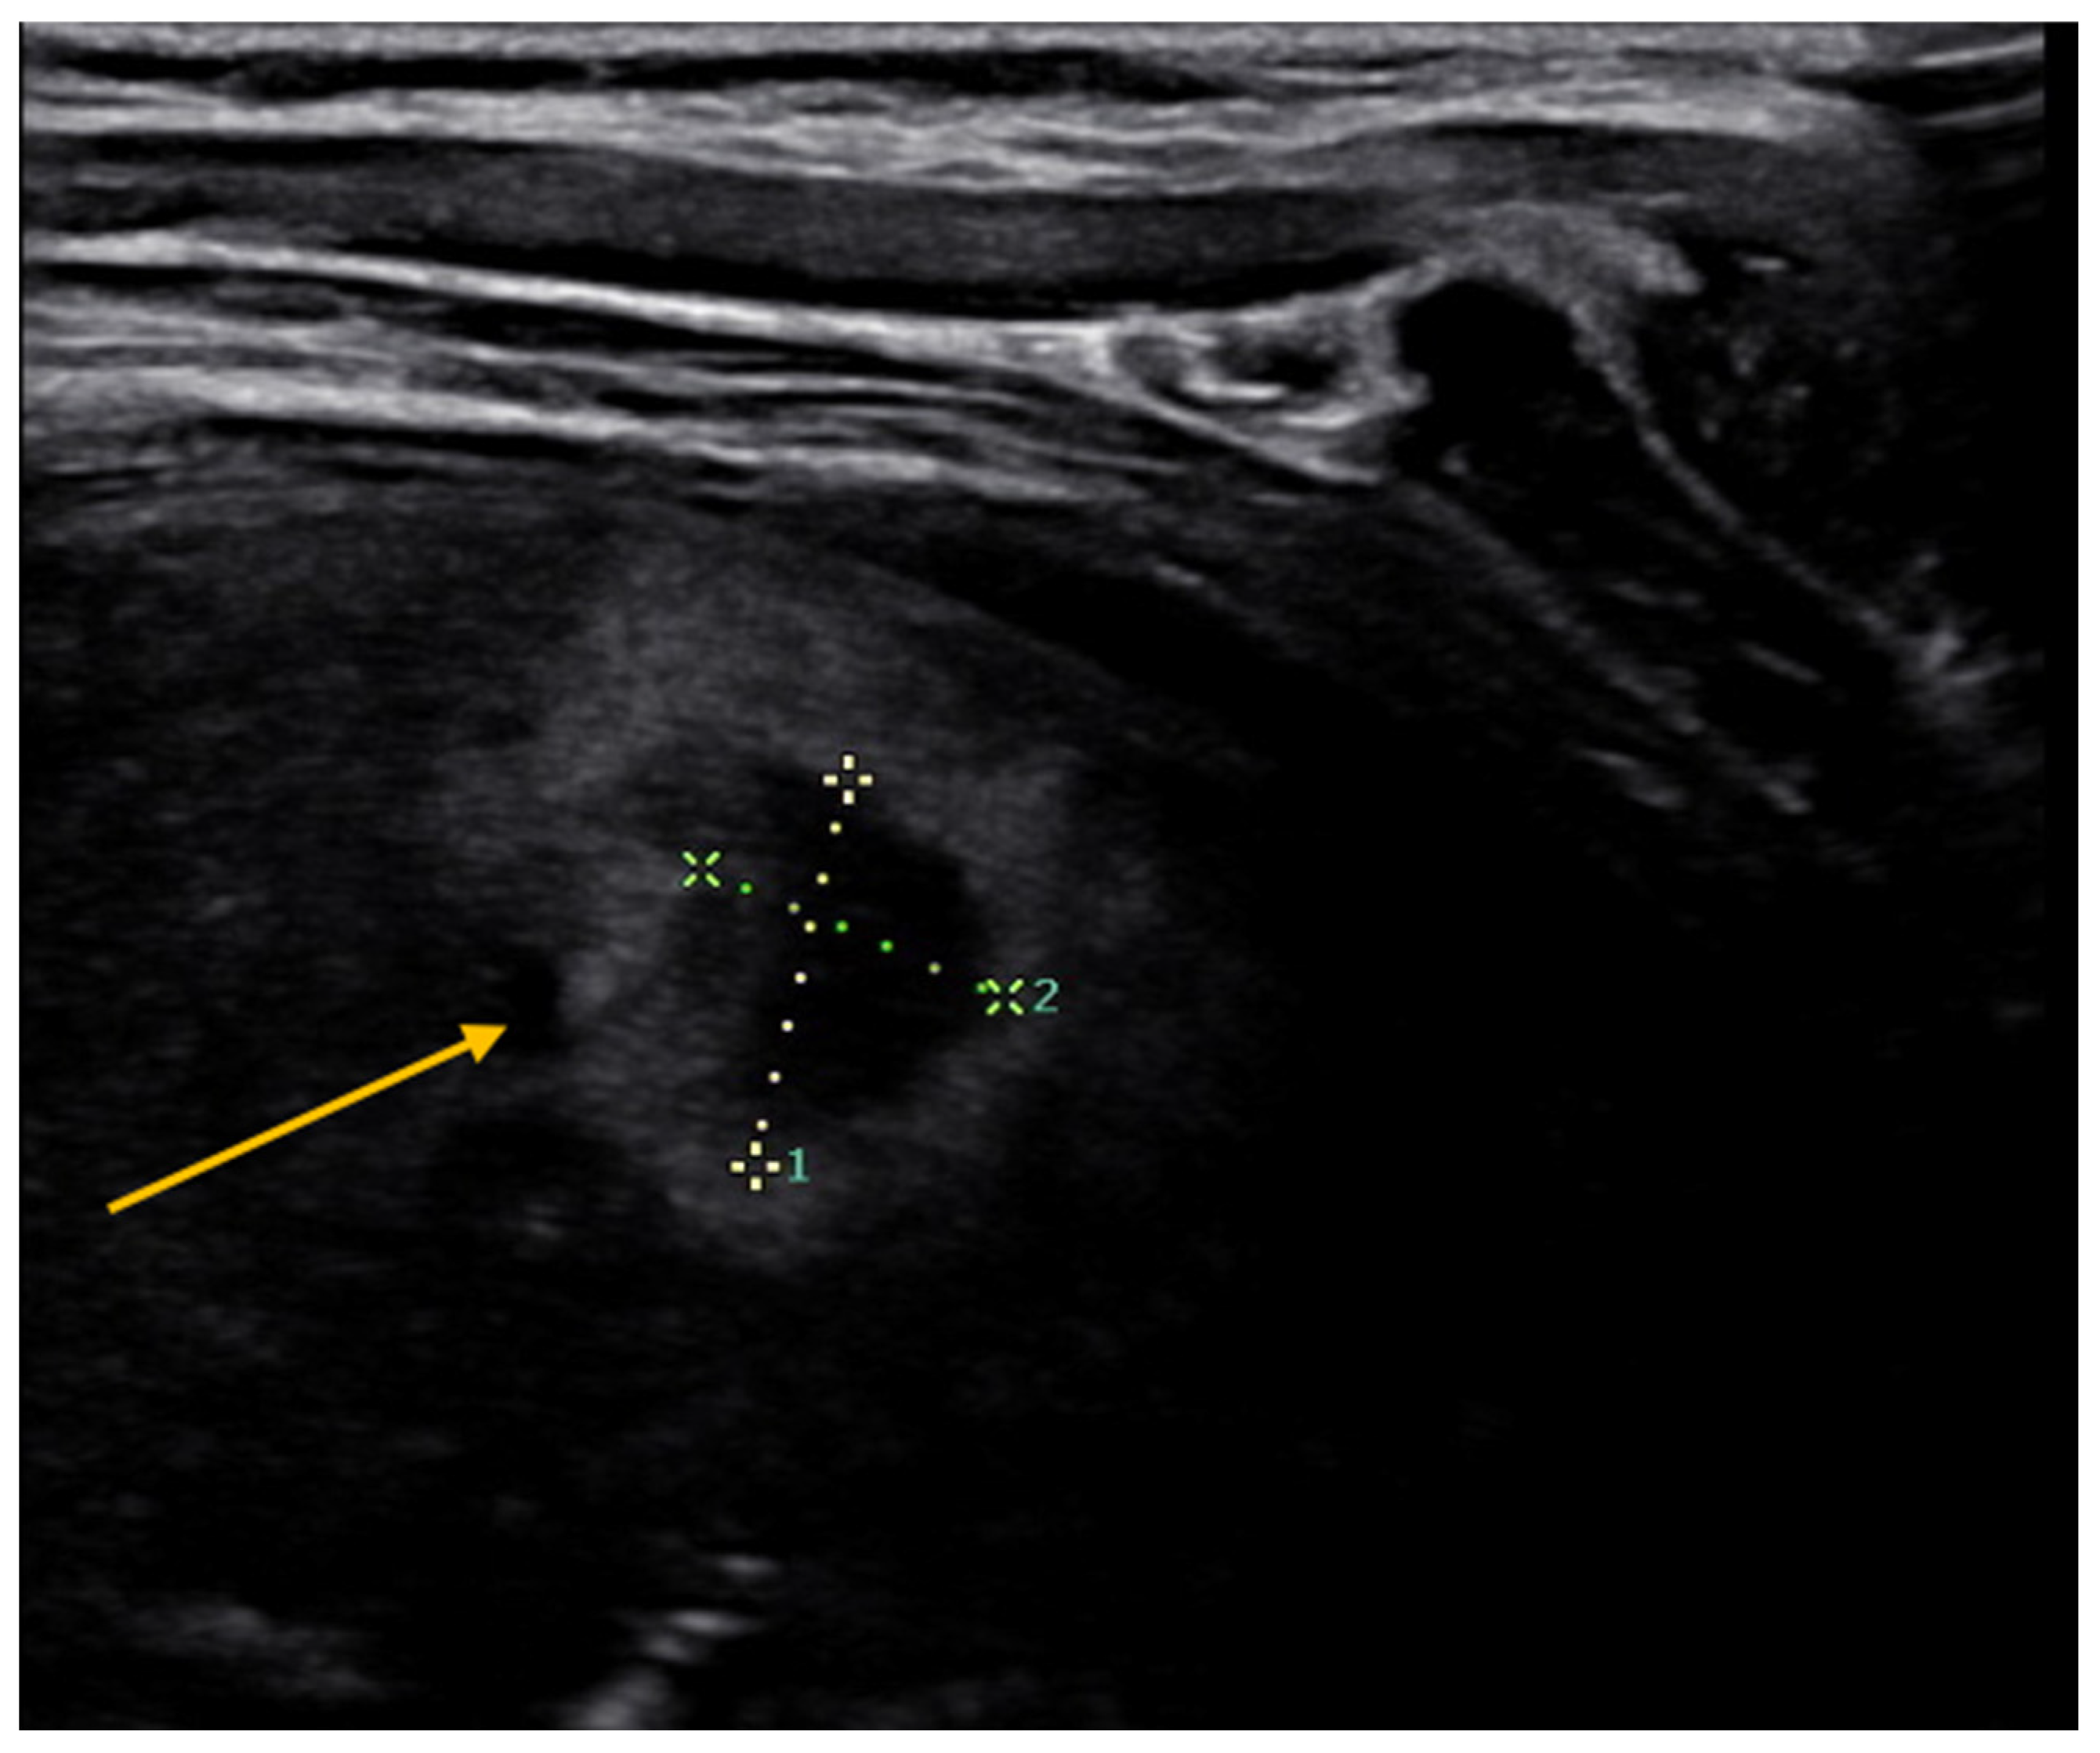

4.6. Pleural Pathologies and Complications of Pneumonia